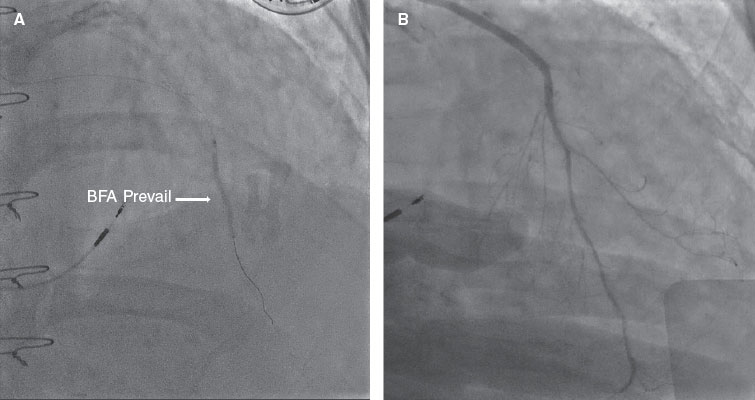

Posteriormente, se avanzó un dispositivo de aspiración Thrombuster II (Kaneka Corp., Japón) hasta el segmento medio de la AMII. La inyección de contraste mostró una oclusión en la anastomosis AMII–DA (figura 1F, flecha). Aunque la trombectomía restableció el flujo, persistía una estenosis grave en el sitio de la anastomosis. Se realizó angioplastia con balón y posteriormente se implantó un balón farmacoactivo (BFA) Prevail de 2,0 × 30 mm (Medtronic, Estados Unidos) a través del injerto y la DA nativa (figura 2A, flecha). La angiografía final mostró un excelente flujo distal (figura 2B; vídeo 2 del material adicional), resolución del segmento ST y mejoría hemodinámica.

Figura 2.